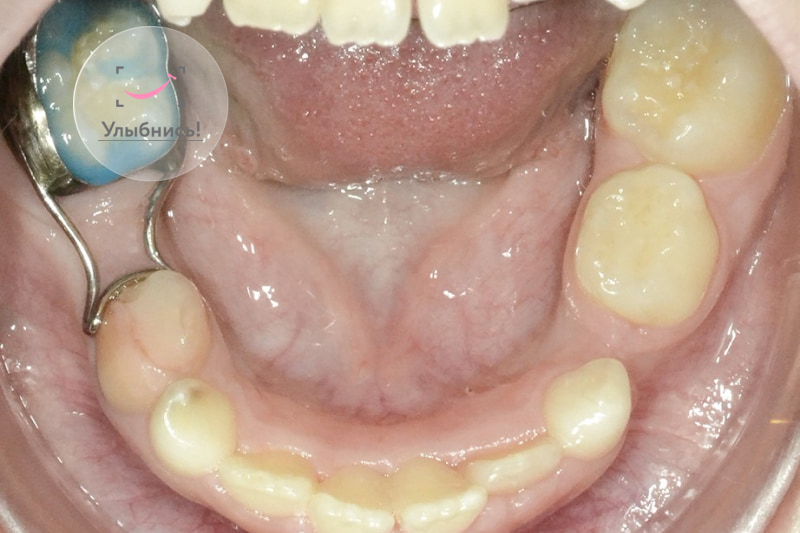

Фото до и после лечения

Фотогалерея